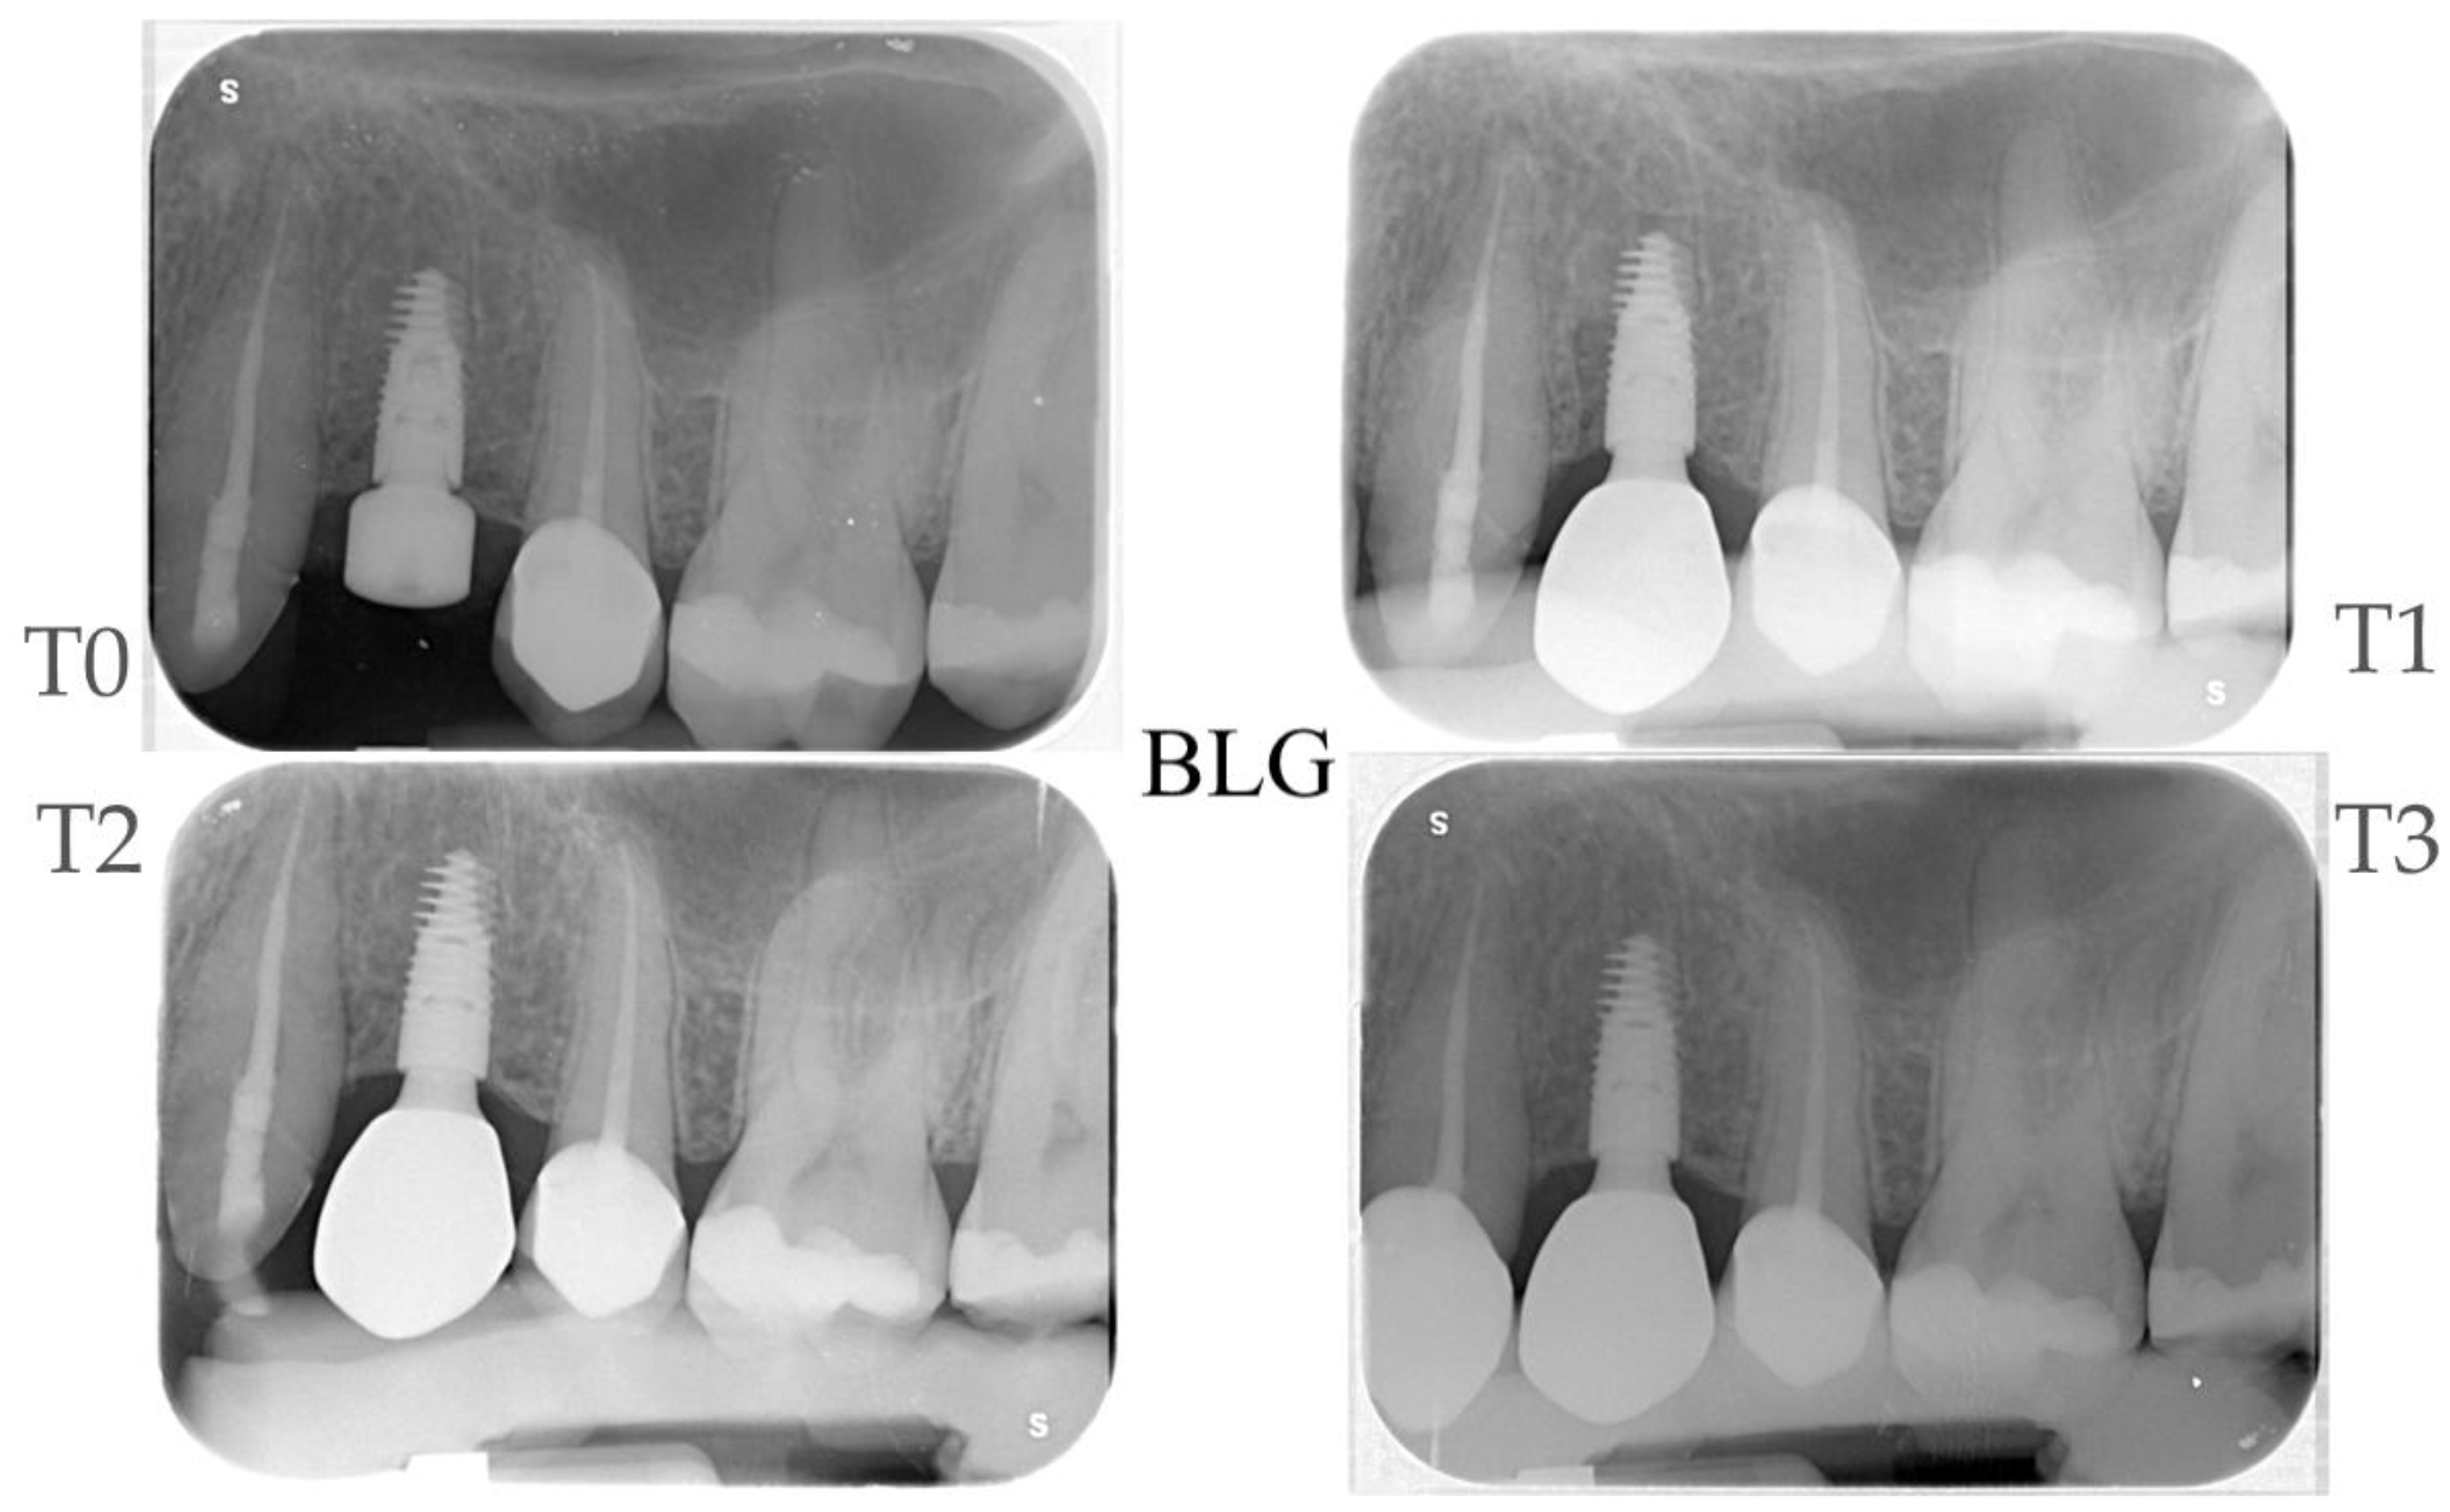

2.4. Radiographic Evaluations

| Time Points | MBM Control Group Δ (CI 95%) ** | p-Value | Bone Loss Control Group Δ (CI 95%) ** | MBM Test Group Δ (CI 95%) * | p-Value | Bone Loss Test Group Δ (CI 95%) ** | MBM Test vs. Control Δ (CI 95%) | p-Value |

|---|---|---|---|---|---|---|---|---|

| T1–T0 | −0.44 (−0.67; −0.21) | <0.01 | −0.44 (−0.67; −0.21) | −0.65 (−0.89; −0.42) | <0.01 | 0 | −0.21 (−0.54; 0.11) | 0.195 |

| T2–T0 | −0.49 (−0.72; −0.26) | <0.01 | −0.49 (−0.72; −0.26) | −0.72 (−0.95; −0.49) | <0.01 | 0 | −0.23 (−0.55; 0.10) | 0.168 |

| T3–T0 | −0.52 (−0.75; −0.29) | <0.01 | −0.52 (−0.75; −0.29) | −0.60 (−0.83; −0.36) | <0.01 | 0 | −0.07 (−0.40; 0.25) | 0.657 |